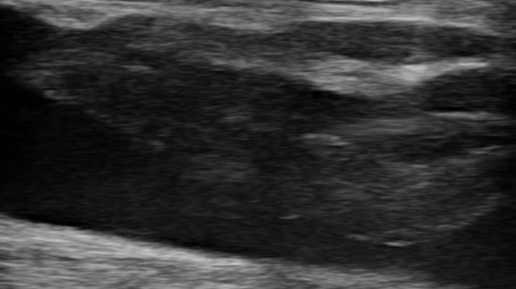

Флотирующий тромбоз бедренной вены (УЗИ)